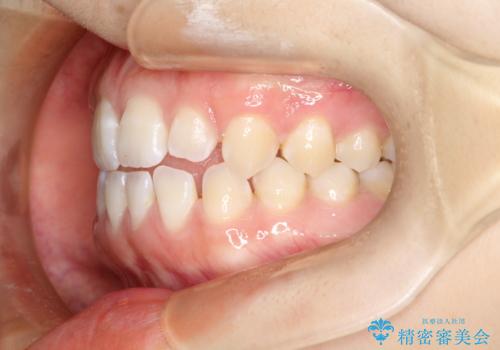

前歯の隙間を閉じたい インビザラインによる矯正

- 上下の前歯に隙間があるとのことで来院されました。

インビザラインにて隙間を閉じる矯正を行いました。

使用時間を守っていただけたので、比較的スムーズに矯正を終了することができました。